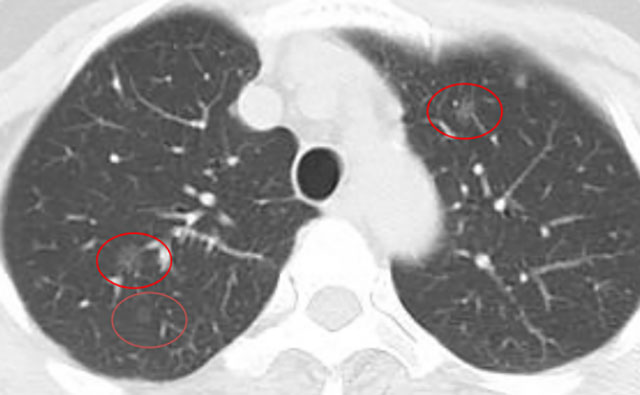

几年前,一位阿姨体检发现双肺多发10余个磨玻璃结节,最大位于右肺上叶,约9mm。当时判断:多为低风险,医生建议半年随访。

几年前影像展示与分析,5mm层厚、无薄层。

上图中红色圈原位癌可能性较大,尤其右肺上叶尖段二个结节,可见血管增粗及血管弯5mm层厚,无薄层重建;橙色圈多考虑不典型增生可能性大;黄色圈大概只是肺泡上皮增生;绿色圈考虑是良性的。